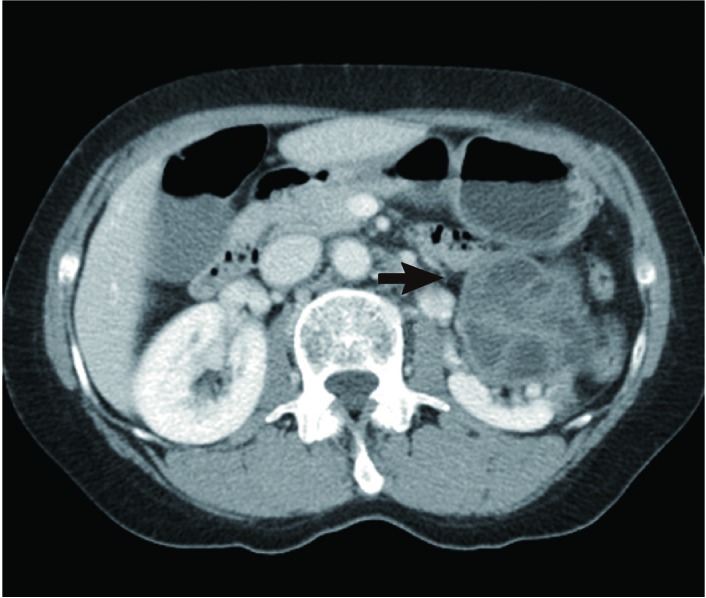

A computed tomography scan of the abdomen and pelvis demonstrated a 6.2-cm left renal cystic lesion in the upper to midpole of the kidney with soft tissue infiltration to anterior perirenal fascia. The cyst had irregular wall thickening and heterogeneous attenuation (Fig. 1). The right kidney and ureter were normal and there was no ascites or lymphadenopathy. Other organs were without definite abnormalities.

Fig. 1

A cystic renal mass (arrow) at the left kidney upper pole, 6.2 cm in size with multiseptation, showing irregular wall thickening, heterogeneous attenuation, and soft tissue infiltration.

Fig. 1 A cystic renal mass (arrow) at the left kidney upper pole, 6.2 cm in size with multiseptation, showing irregular wall thickening, heterogeneous attenuation, and soft tissue infiltration.